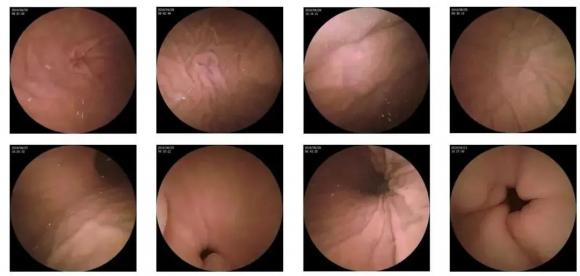

胃鏡檢查時,醫生在直視下觀察胃黏膜的,加上放大、染色、取活檢等技術,能夠最大限度上發現早期胃癌。

可以觀察消化道管壁的表面結構和血管、腺管等有無異常,從而早期發現病變,并可進行活檢確診。同時,內鏡檢查還可以完整地觀察整個胃的結構,基本上可以做到觀察無死角。

因此,發現消化管壁癌最敏感、最可靠的檢查還是胃鏡。